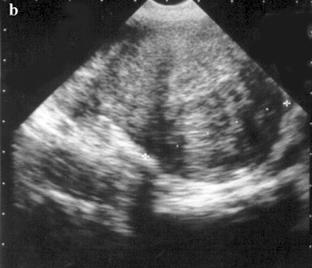

Fibrom uterin interstitial sau intramural. Imaginea ecografica a fibromului, in comparatie cu miometrul, este neomogena (a). Ea poate fi identificata datorita deformarii convexitatii peretelui uterin si prin evidentierea planului de clivaj, respectiv a capsulei care, uneori, prezinta calcificari (b).

Imaginea ecografica a uterului polifibromatos, multinodular. Importante sunt analizarea structurii si efectuarea biometriei la fiecare nodul pentru a putea aprecia caracterul evolutiv de la o examinare la alta